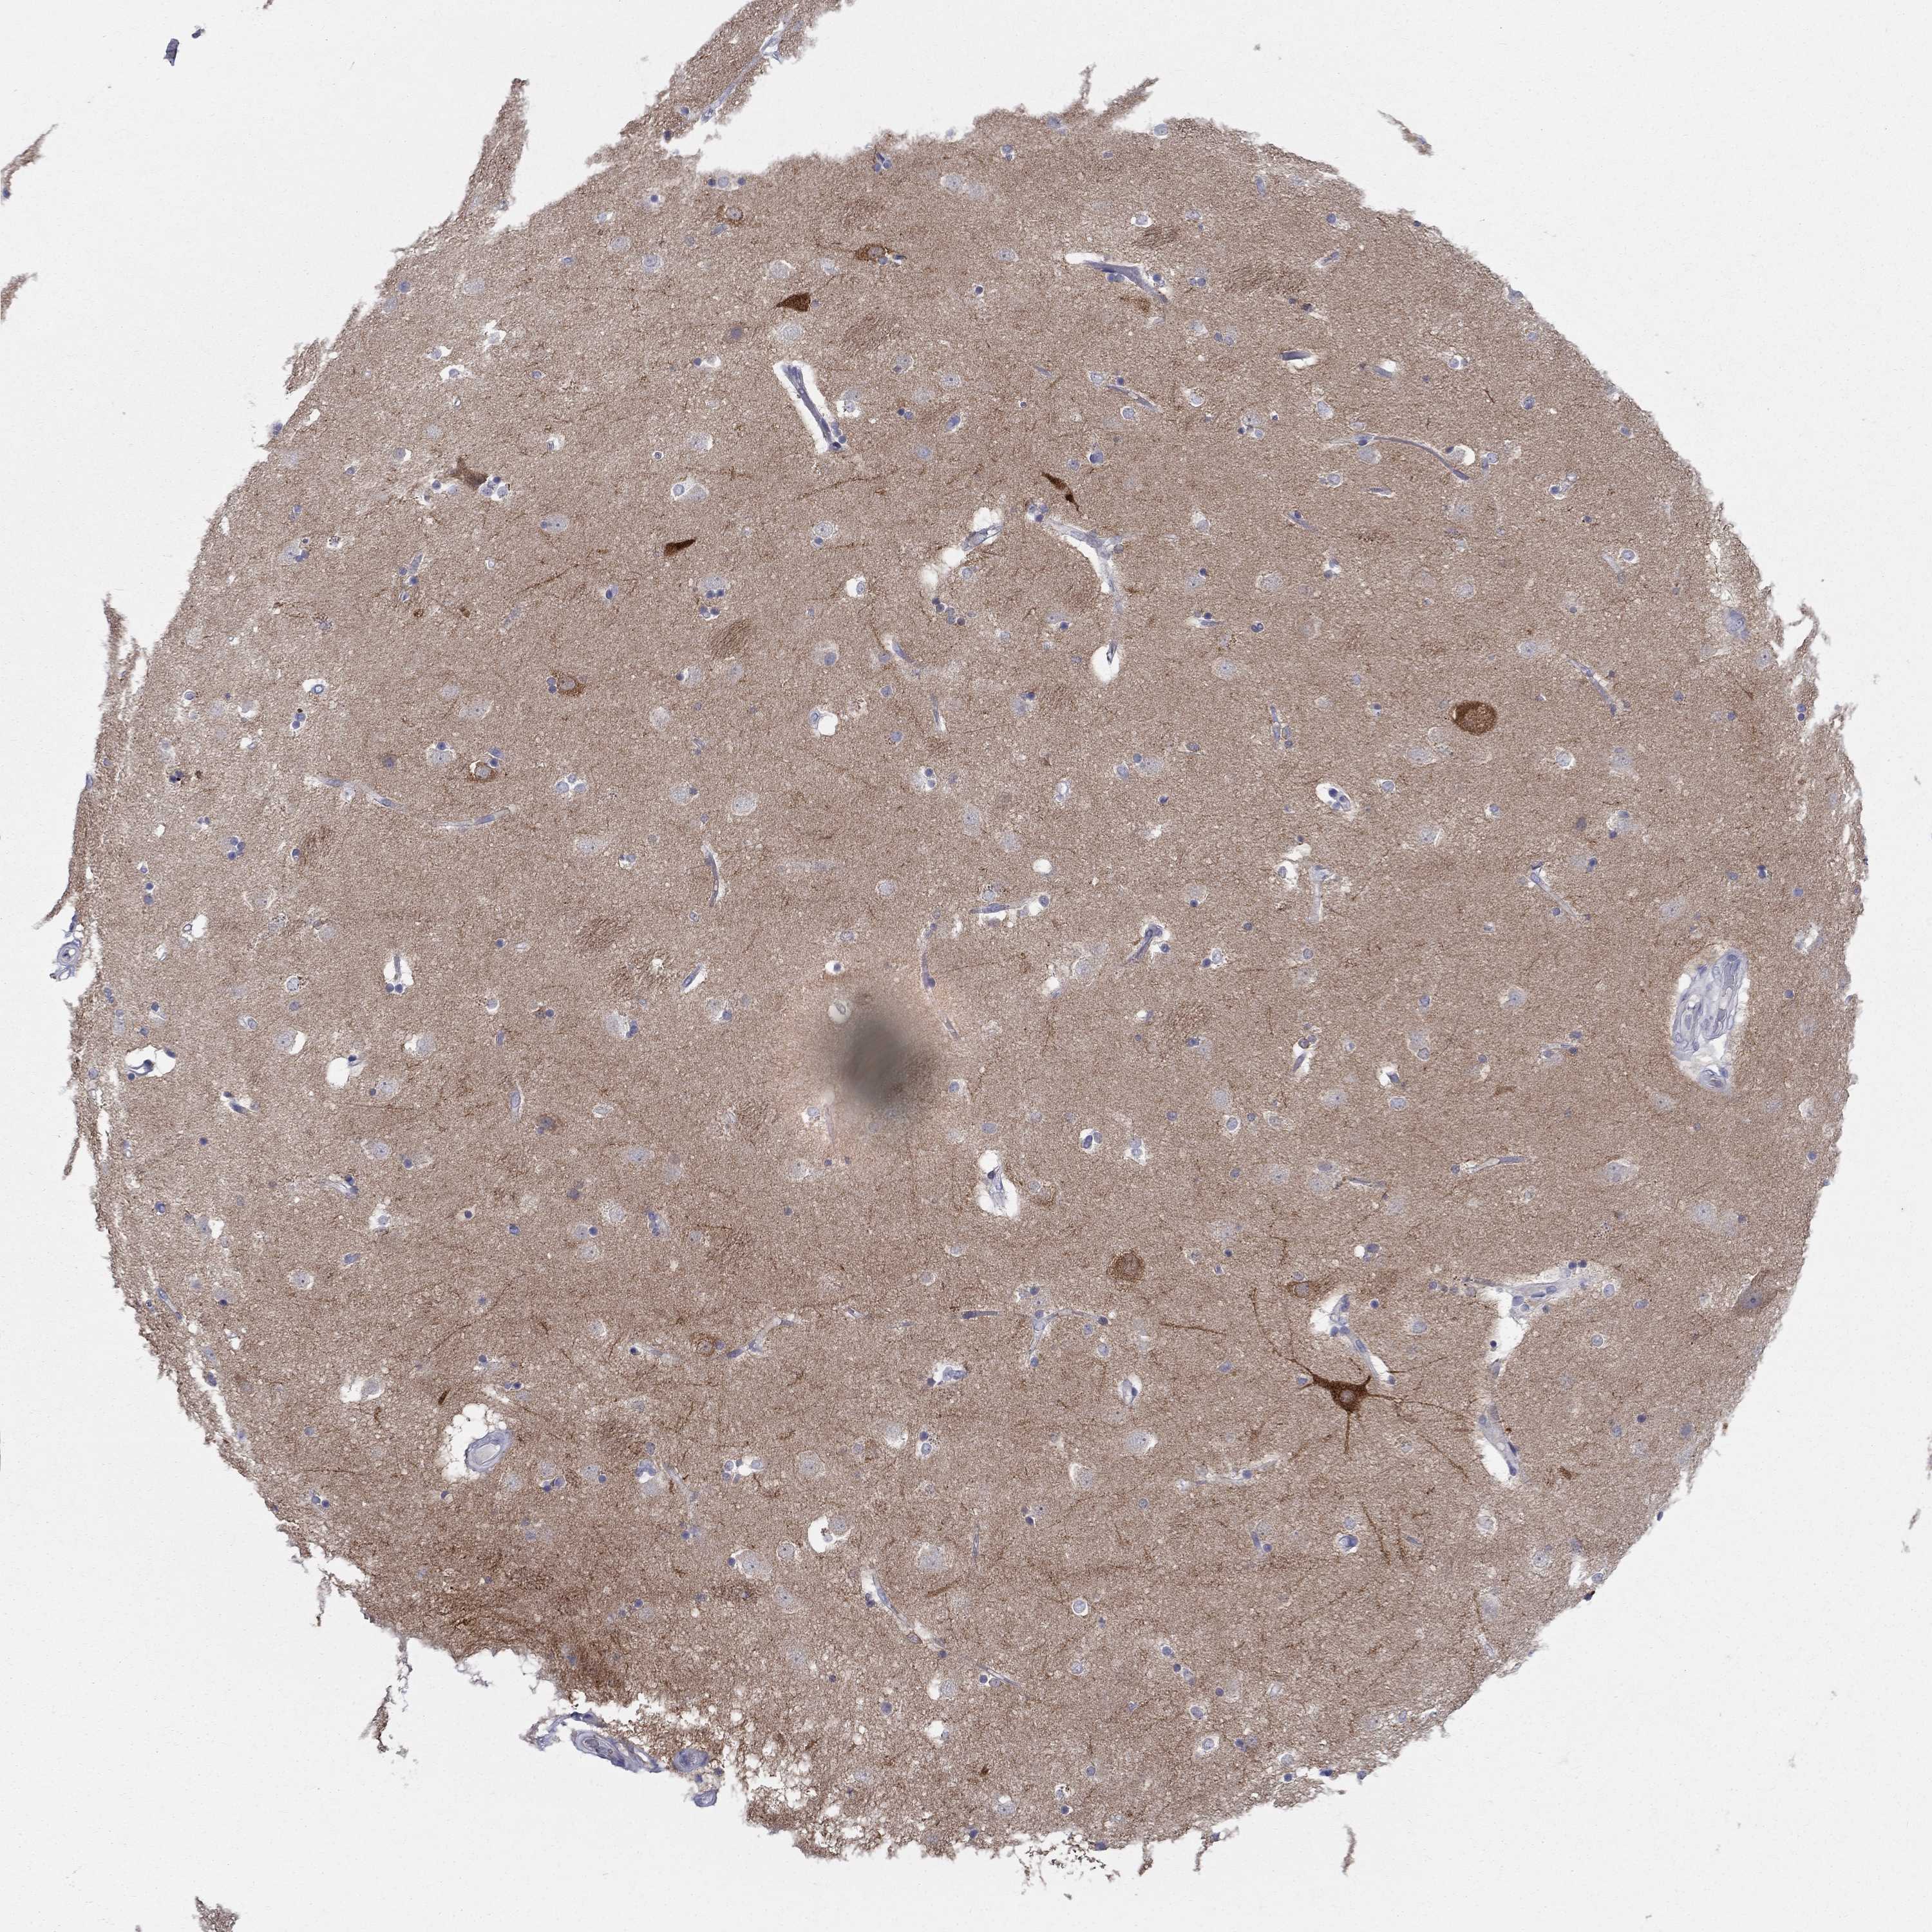

Cytoplasmic and dendritic/axonal immunoreactivity in neurons, most abundant in areas of the cerebral cortex (LIV-V), nucleus accumbens as well as thalamus or certain midbrain and pontine/medullar nuclei.

Manually selected location of the protein positivity, observed by immunofluorescence staining in mouse brain.